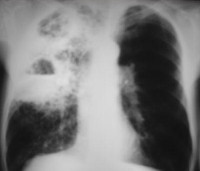

• Методы лучевой диагностики. На рентгенографии грудной клетки и на КТ лёгких выявляются участки гомогенной инфильтрации, захватывающие долю лёгкого, чаще верхнюю справа. Иногда поражаются 2 доли, либо присутствуют дополнительные очаги в том же или противоположном лёгком. На 2-3 сутки появляются полости распада, признаки выпота в полости плевры.

Заболевание следует дифференцировать с туберкулёзом лёгких. Рентгенологическая картина воспаления клебсиеллёзной этиологии напоминает казеозную пневмонию, туберкулёзный лобит. В целях дифференциальной диагностики пациент осматривается фтизиатром. Выполняются анализы патологического материала экспресс-методами и посевы на микобактерии туберкулёза.